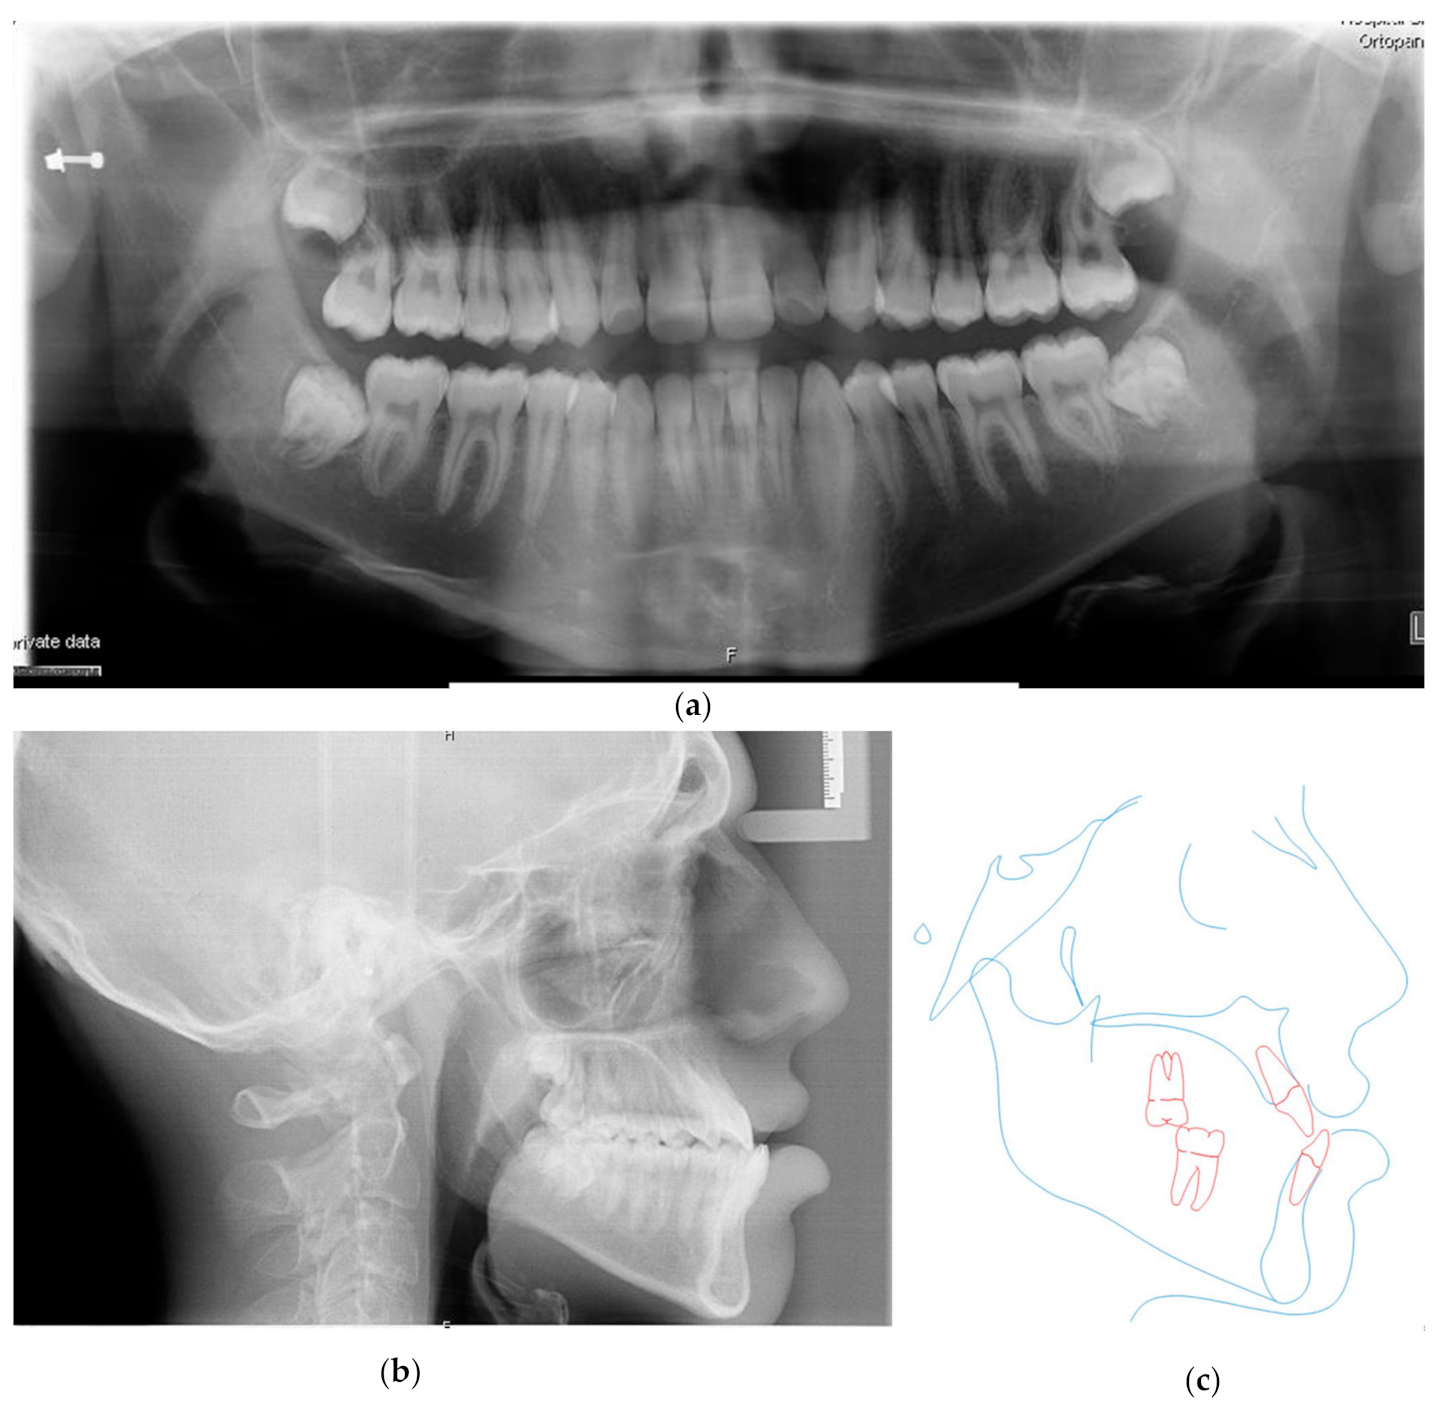

3. Results

3.4. Treatment Results